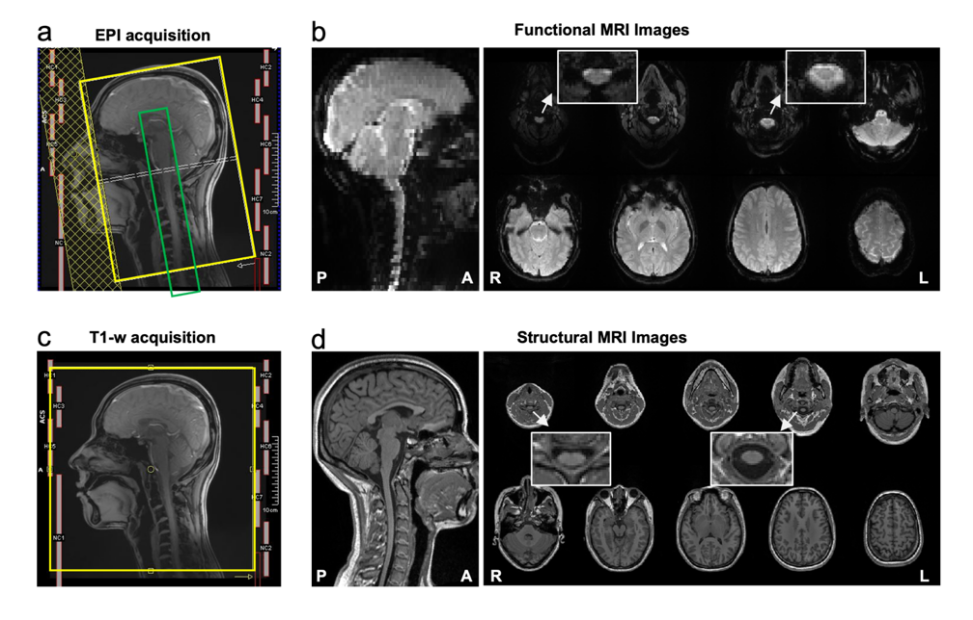

CoSpine成像方案基于西门子 3T Prisma 磁共振系统,实现了覆盖大脑、脑干、小脑及颈段脊髓的单视野同步采集(见图1)。该方案融合多频带并行采集与并行重建算法,在保持1.5毫米高空间分辨率的同时,大幅提升了时间采样效率与图像质量。这一成像策略使皮层—脑干—脊髓神经信号得以在一次扫描中连续获取,为系统性研究脑–脊髓功能交互研究奠定了方法学基础。

图1. CoSpine功能与结构成像的采集方案及示意图